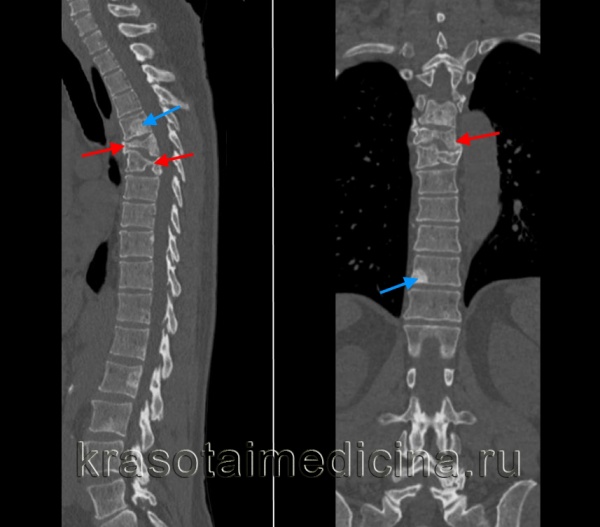

КТ ГОП. Патологический перелом 6 и 7 грудных позвонков (красная стрелка) на фоне вторичного поражения позвонков (синяя стрелка).